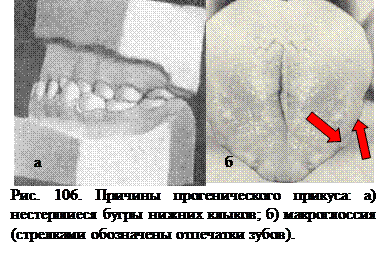

Развитию прогенического, (мезиального) прикуса, способствует ротовое дыхание с гипертрофией небной миндалины; макроглоссия.

В развитии прогенического (мезиального) прикуса, в особенности принужденной его формы, основную роль играют нестершиеся бугры молочных клыков и неправильное положение головы во время сна.

Патогенетическим фактором истинной прогении многие авторы считают большой язык, макроглоссию, который своим давлением способствует чрезмерному развитию и росту нижней челюсти.

Основная причина развития ложной прогении - это нестершиеся бугры молочных клыков, которые мешают правильному смыканию боковых зубов.